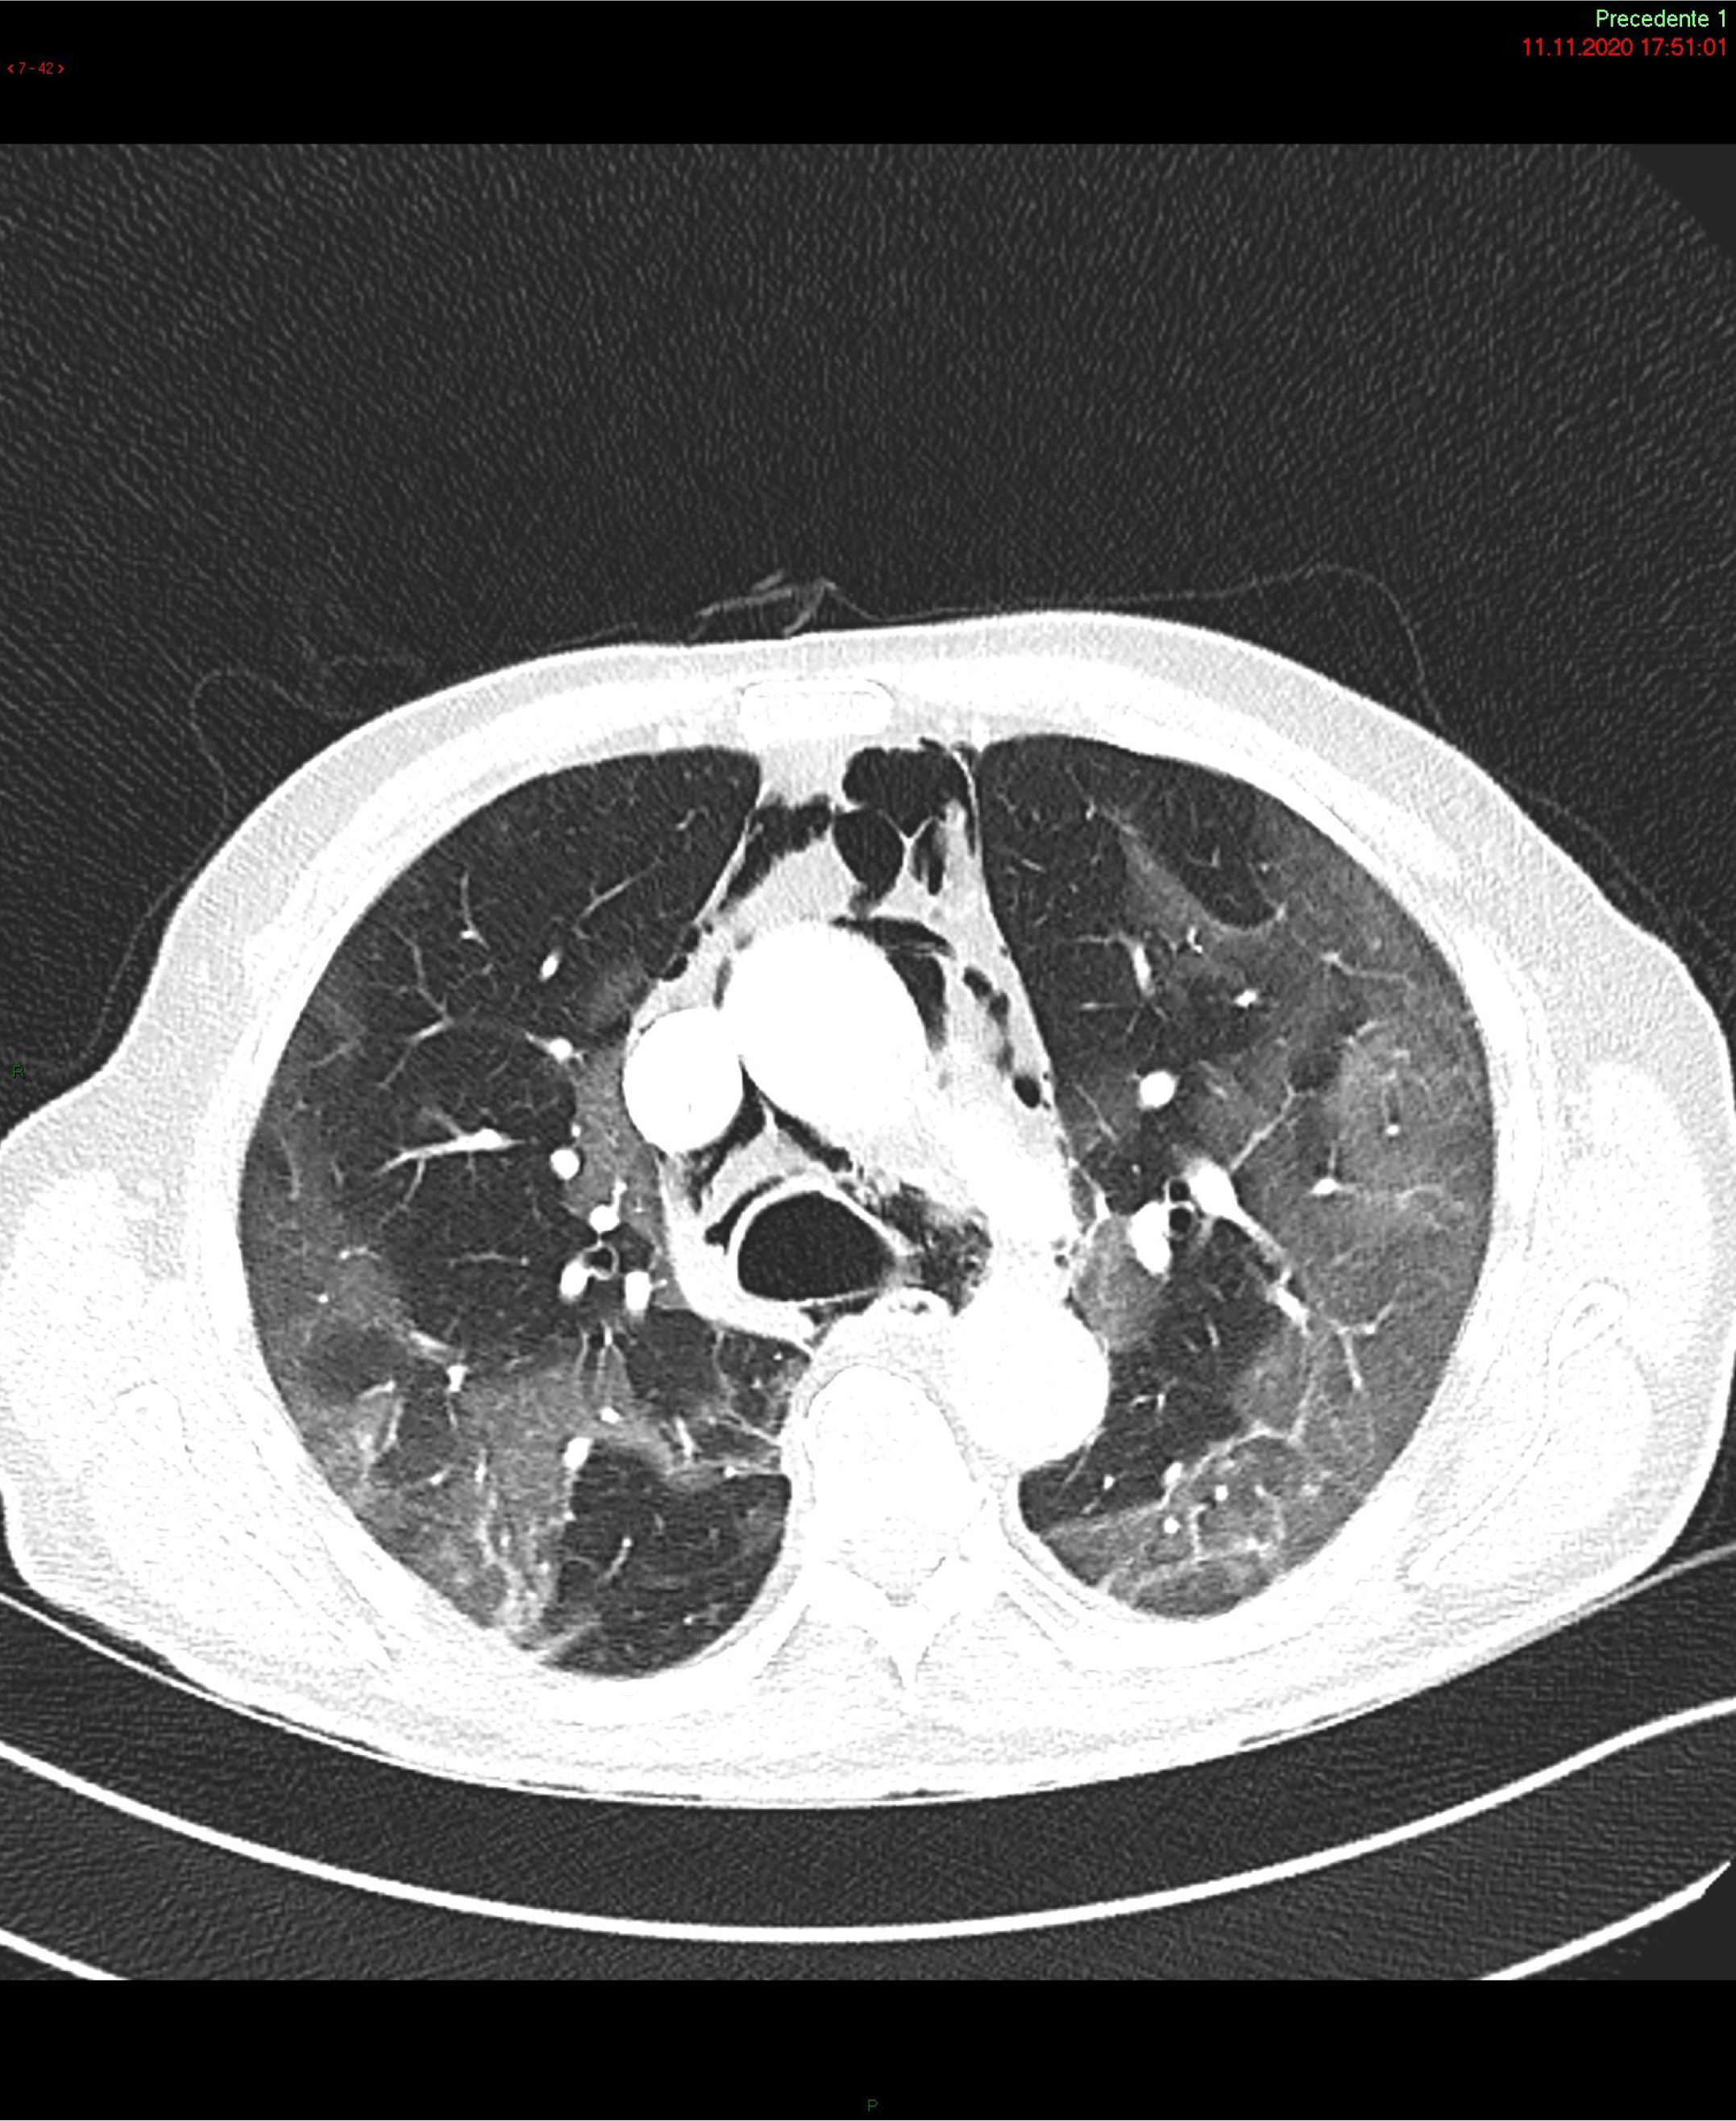

Figure 1: Chest computed tomography scan: air leakage and dissection along bronchovascular sheaths with pulmonary interstitial emphysema and pneumomediastinum, widely extending along the muscle bundles of the chest and neck causing subcutaneous emphysema.

SP and Subcutaneous Emphysema (SE) have been reported as uncommon clinical findings in patient with SARS- CoV-2 infection (Figure). Case series of patients with COVID-19 pneumonia and SP not on MV [9] showed that the SP was more likely to develop on 13th – 17th day since the onset of symptoms [9]. The most common associated conditions reported were older age, obesity and dyslipidemia, hypertension, diabetes mellitus, renal disease and asthma. Its occurrence is believed to be related to an increased pressure in the interstitial space, which may favor alveolar rupture hence resulting in pneumomediastinum [1012]. Therefore, invasive MV as well as coughing, emesis, a strong Valsalva maneuver or asthma exacerbation are considered possible triggering events [1,9,13,14]. Additional predisposing factors are high-dose corticosteroid therapy and anatomical anomalies [1,4, 9].